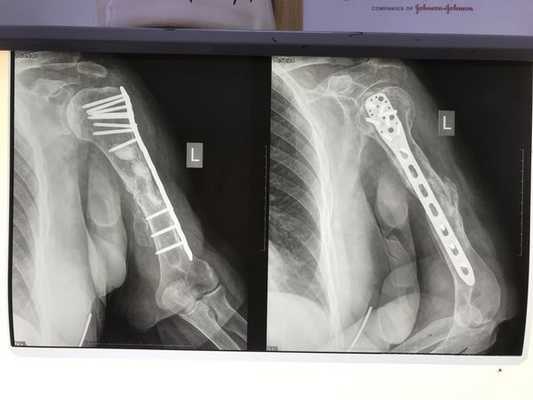

Через год выяснилось, что перелом не сросся. Пластина была нестабильной, женщина жаловалась на хруст и щелчки в области плеча.

Пациентку снова госпитализировали на оперативное лечение. Пластину удалили. При осмотре обнаружили, что отломки кости неправильной формы, склерозированы на большом протяжении — около 10 см. Это значит, что их плотность увеличилась. Пришлось удалить нежизнеспособные фрагменты кости. После этого стало понятно, что расстояние между отломками очень большое и необходима костная пластика дефекта.

- Первый этап — пластика дефекта по Маскуле. Отломки фиксировали антеградно интрамедуллярным стержнем. Вокруг стержня на протяжении всего дефекта сформировали цементную мантию с добавлением 2 г. Ванкомицина. Мягкие ткани и рану ушили. Послеоперационный период прошёл гладко.

- Через пять недель провели второй этап лечения. Из гребня подвздошной кости взяли губчато-кортикальный аутотрансплантат 7 х 2 х 3 см. Выполнили разрез по переднему отделу плеча над плечевым суставом. Стержень удалили. Вокруг цементной мантии сформировалась биологически активная мембрана. Её аккуратно отслоили. В неё уложили аутотрансплантат, мембрану над ним ушили. Таким образом, костный дефект между отломками был заполнен губчато-кортикальным аутотрансплантатом. Отломки фиксированы пластиной LCP PHILOS. Рана ушита. Послеоперационный период прошёл без осложнений.

Пациентка наблюдалась в течение трёх лет после начала лечения. В итоге ложный сустав плечевой кости полностью сросся, аутотрансплантат перестроился и прижился.